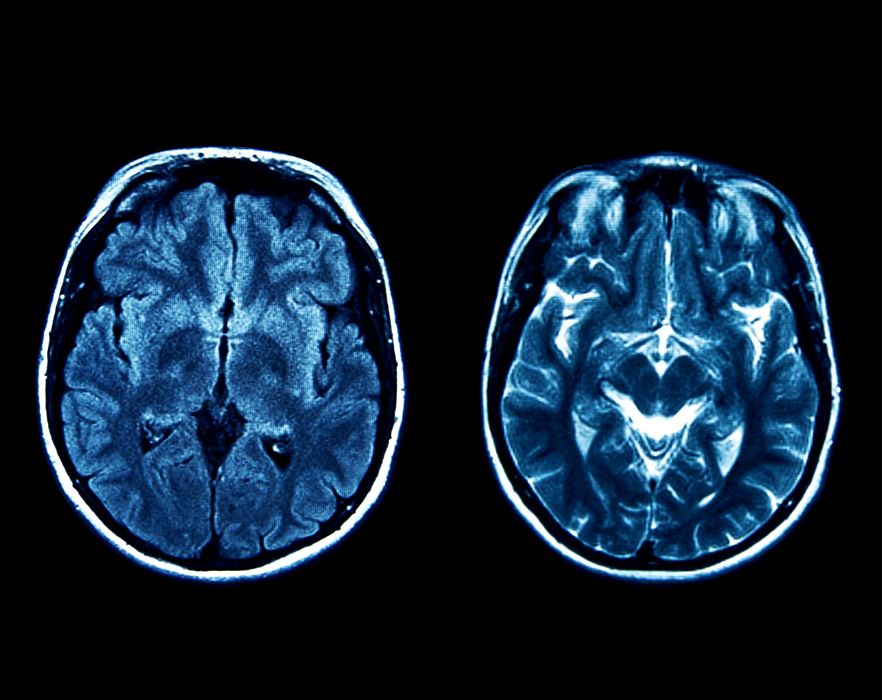

Un antidepresiv ar putea trata tumorile cerebrale

Glioblastomul este o tumoare cerebrală deosebit de agresivă, care în prezent este incurabilă. Medicii oncologi pot prelungi speranța de viață a pacienților prin operații, radioterapie, chimioterapie sau intervenții chirurgicale. Cu toate acestea, jumătate dintre pacienți […]